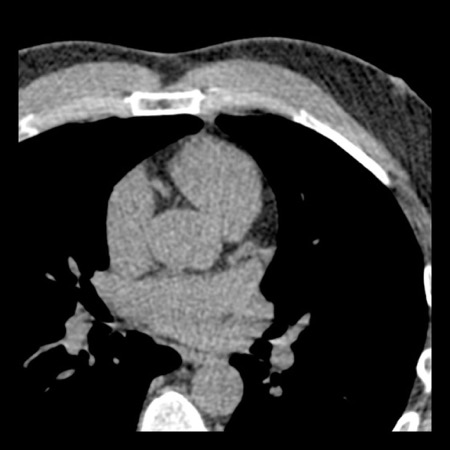

case 2 – CAD-RADS 5/P2/S

First, scroll through the CTA images.

How would you describe the findings on the coronary CTA?

The findings are:

- Stent in the mid

LAD with low-attenuation within the stent suggestive of minimal in-stent

restenosis (<25%). Non-calcified plaque distal to the stent

causing mild stenosis (25-49%). Notice bridging on a short segment in

the distal LAD. - Non-calcified

plaque in the LCX causing mild stenosis (25-49%). - Occlusion of the

proximal OM1 branch with distal filling. - Calcified and

non-calcified plaques in the proximal RCA causing mild (25-49%) stenosis. - Total plaque burden

is moderate based on SIS (four segments including proximal RCA, mid LAD, prox

LCX and OM1).

Due to the occlusion of OM1 branch and presence of the stent, this case

reads as CAD-RADS 5/P2/S, which means that this patient needs further

diagnostic workup.